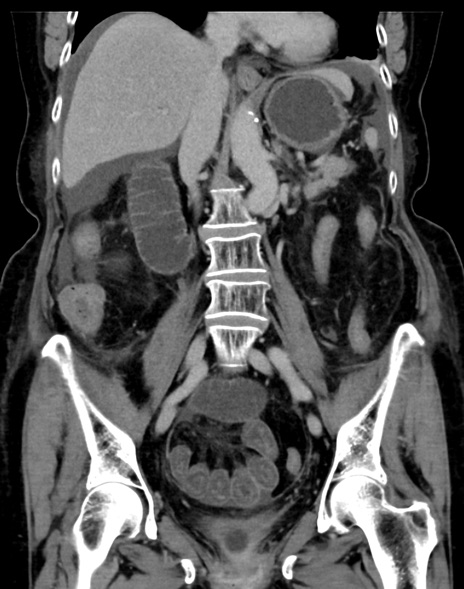

症例13 CT(冠状断像)1日半後